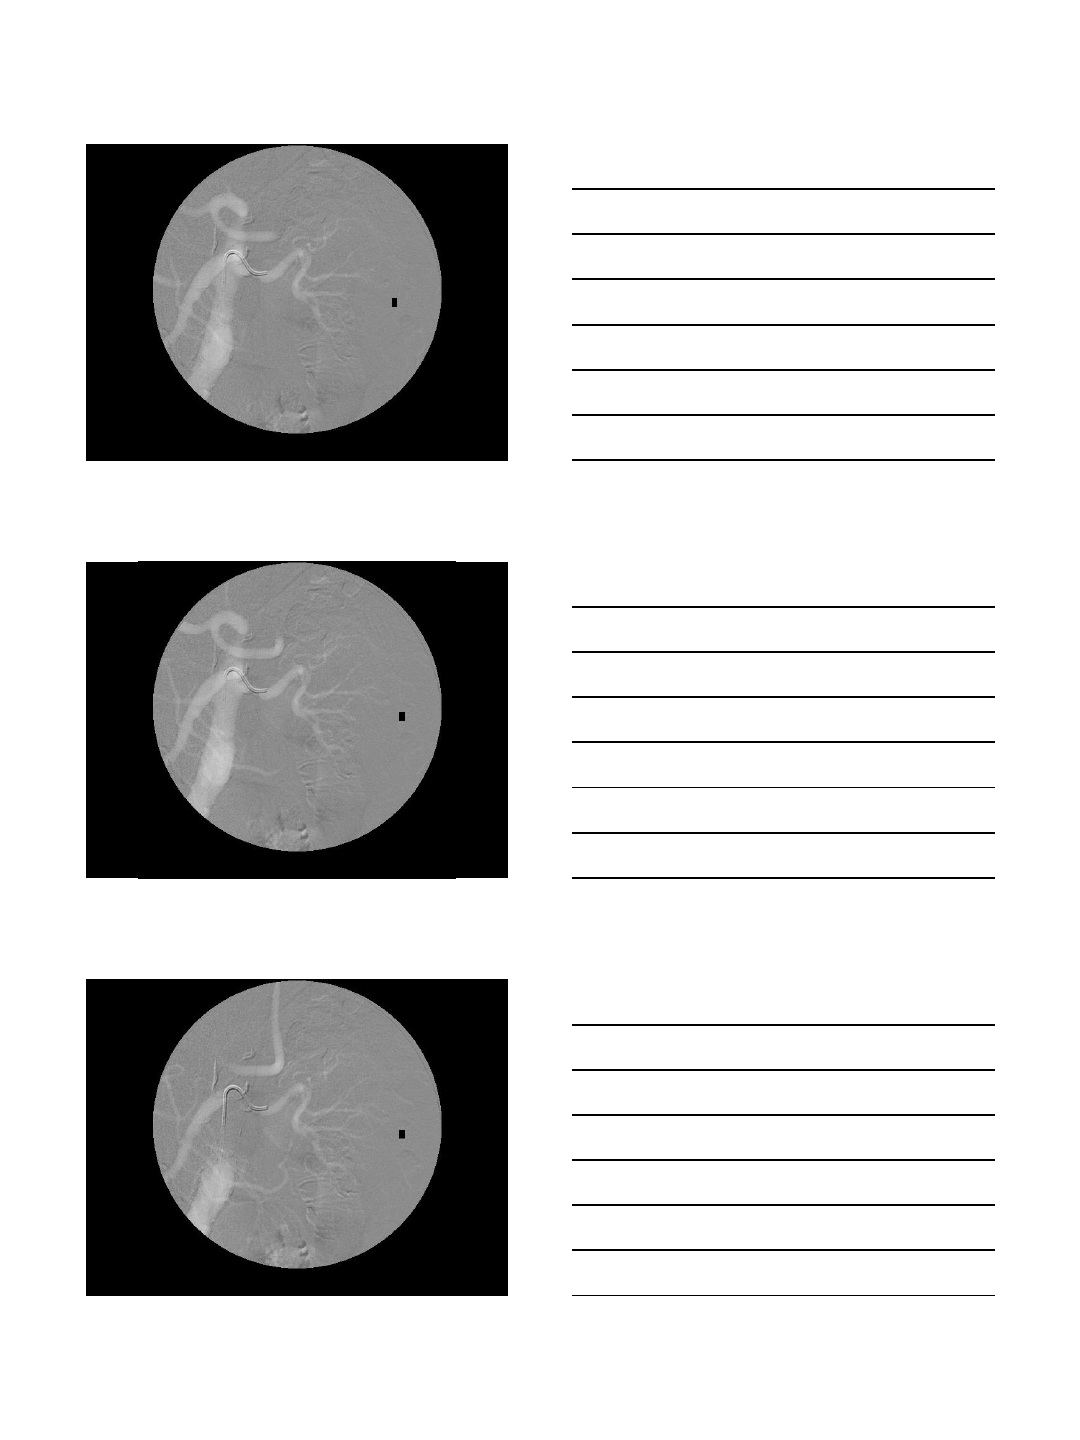

CO2 Portogram in TIPS

TIPS procedures

•AP and oblique views

•Excellent to localize the portal vein

•Wedge injection

•Wedged catheter or balloon catheter

•Gentle injection of 15-20 cc

•Careful in patients with ascites

•Intraparenchymal injection